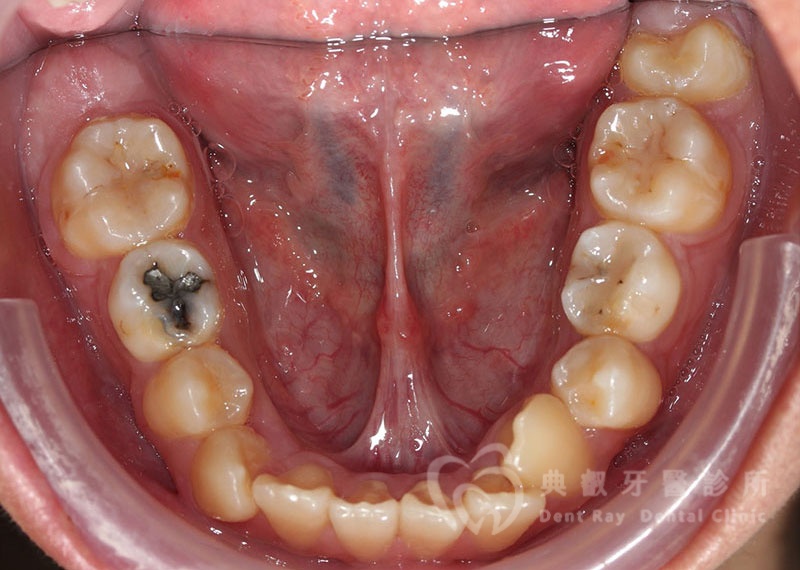

Before

After